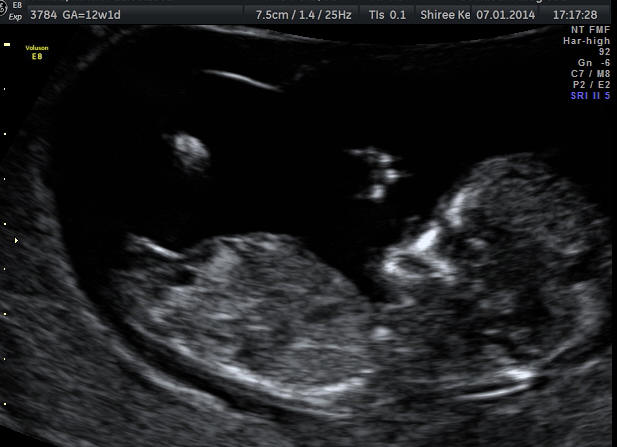

NT scan 12w+1. Guesses please! :)

Attachment 16134